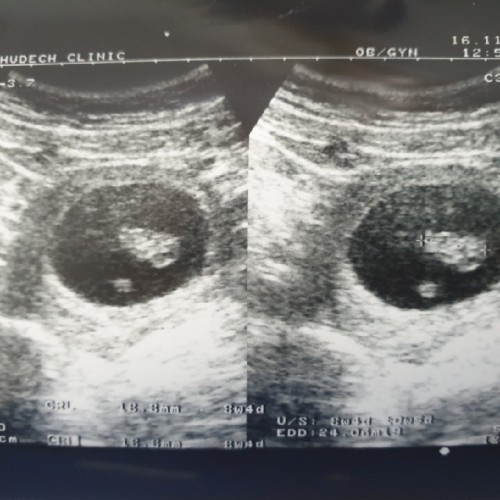

บ้านนี้เจอตอน 6w5d จ้า

เจอตอน 8 สัปดาห์ครับ

8wจ้า ตอน5wก็มีแต่ถุง